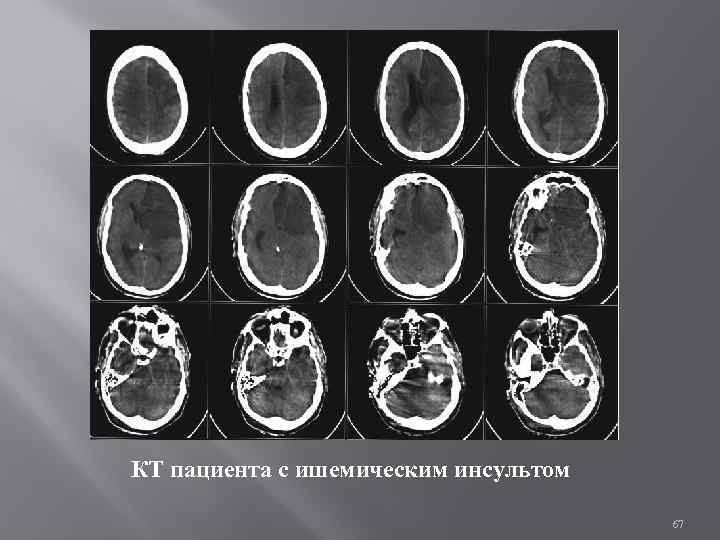

Компьютерная томография головы Компьютерная томография (КТ) или компьютерная аксиальная томография (КАТ) использует серии рентгеновских лучей, направленных на голову, с большого количества разных направлений. Обычно её используют для быстрой визуализации ЧМТ. При КТ используют компьютерную программу, что осуществляет цифровые интегральные вычисления (инверсию преобразования Радона) измеряемой серии рентгеновских лучей. Она вычисляет, насколько эти лучи абсорбируются объёмом головного мозга. Обычно информация представлена в виде срезов мозга. Диффузная оптическая томография (ДОТ) — способ медицинской визуализации, использующий инфракрасное излучение для изображения тела человека. Технология измеряет оптическую абсорбцию гемоглобина и опирается на его спектр поглощения в зависимости от насыщения кислородом.

КТ пациента с ишемическим инсультом 67